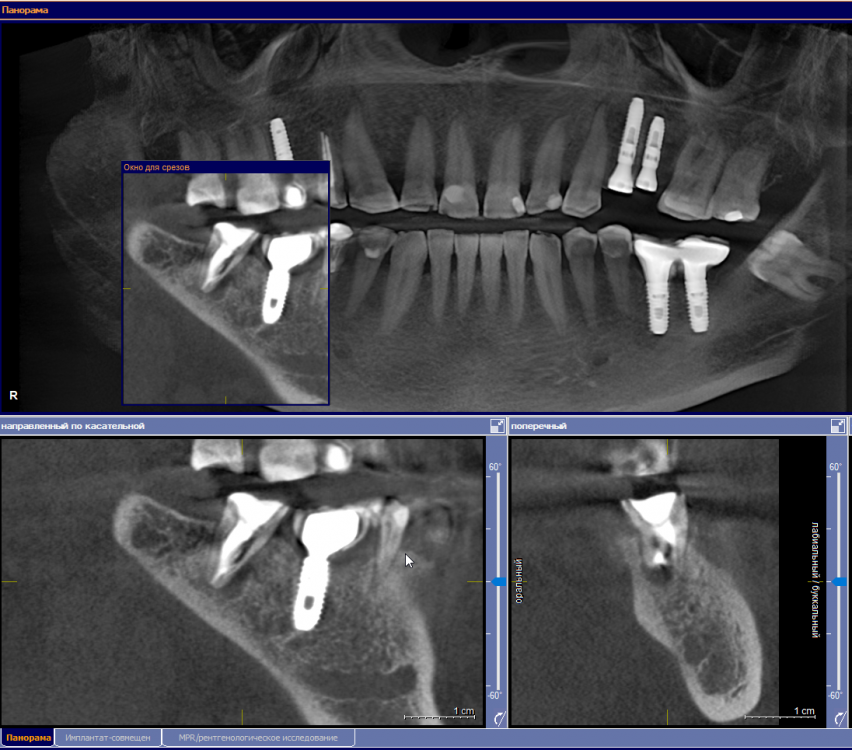

se77777 Опубликовано 5 апреля, 2023 Автор Поделиться Опубликовано 5 апреля, 2023 Спасибо. Ссылка на комментарий

red_butler Опубликовано 5 апреля, 2023 Поделиться Опубликовано 5 апреля, 2023 по Кт все нормально, нужно смотреть очно 1 Ссылка на комментарий

IvanK Опубликовано 6 апреля, 2023 Поделиться Опубликовано 6 апреля, 2023 Здравствуйте Покажитесь Вашему врачу Ссылка на комментарий